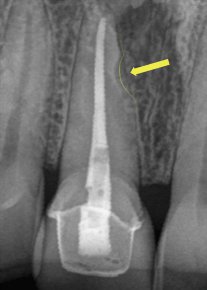

На двухмерном снимке просветление на боковой поверхности корня зуба наталкивает на предположение о нарушении целостности стенки корня. Это может расцениваться как патология.

Для уточнения результата был сделан трехмерный снимок.

На трехмерном снимке стало видно, что просветление сформировалось в результате наложения анатомических структур: резцового канала и корня зуба. Беспокоиться тут не о чем, это особенности анатомии.